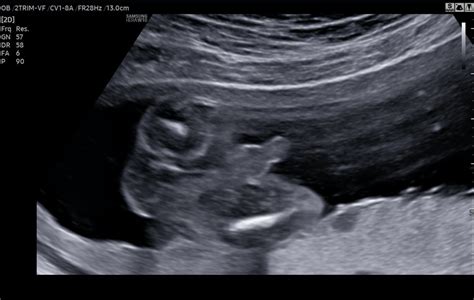

Ultrazvuk v 20. týždni tehotenstva je často nazývaný aj „veľký ultrazvuk“ alebo morfologický ultrazvuk. Toto vyšetrenie sa robí v čase, ktorý je ideálny na zhodnotenie detailnejšej morfológie plodu. Lekár počas tohto vyšetrenia dôkladne prezrie všetky orgány a časti tela bábätka, aby skontroloval ich správny vývoj a usporiadanie. Zameriava sa na končatiny, tvárové štruktúry, vnútorné orgány a ďalšie dôležité anatomické znaky. Cieľom je odhaliť prípadné vývojové chyby, ktoré sa v tomto štádiu už dajú pomerne spoľahlivo diagnostikovať.

Pri tomto vyšetrení sa už typicky prechádza na transabdominálny ultrazvuk, pri ktorom lekár pozerá dieťatko cez brušnú stenu. Pre lepšiu viditeľnosť sa pri tomto type vyšetrenia odporúča mať plný močový mechúr, pretože naplnený močový mechúr funguje ako akustický „okenník“, ktorý zlepšuje prenos ultrazvukových vĺn a tým aj kvalitu obrazu. Lekár nanesie na vaše brucho priehľadný gél a následne pomocou sondy jemným tlakom prechádza po brušnej stene. Pre bábätko z tohto jemného tlaku nehrozí žiadne poškodenie.